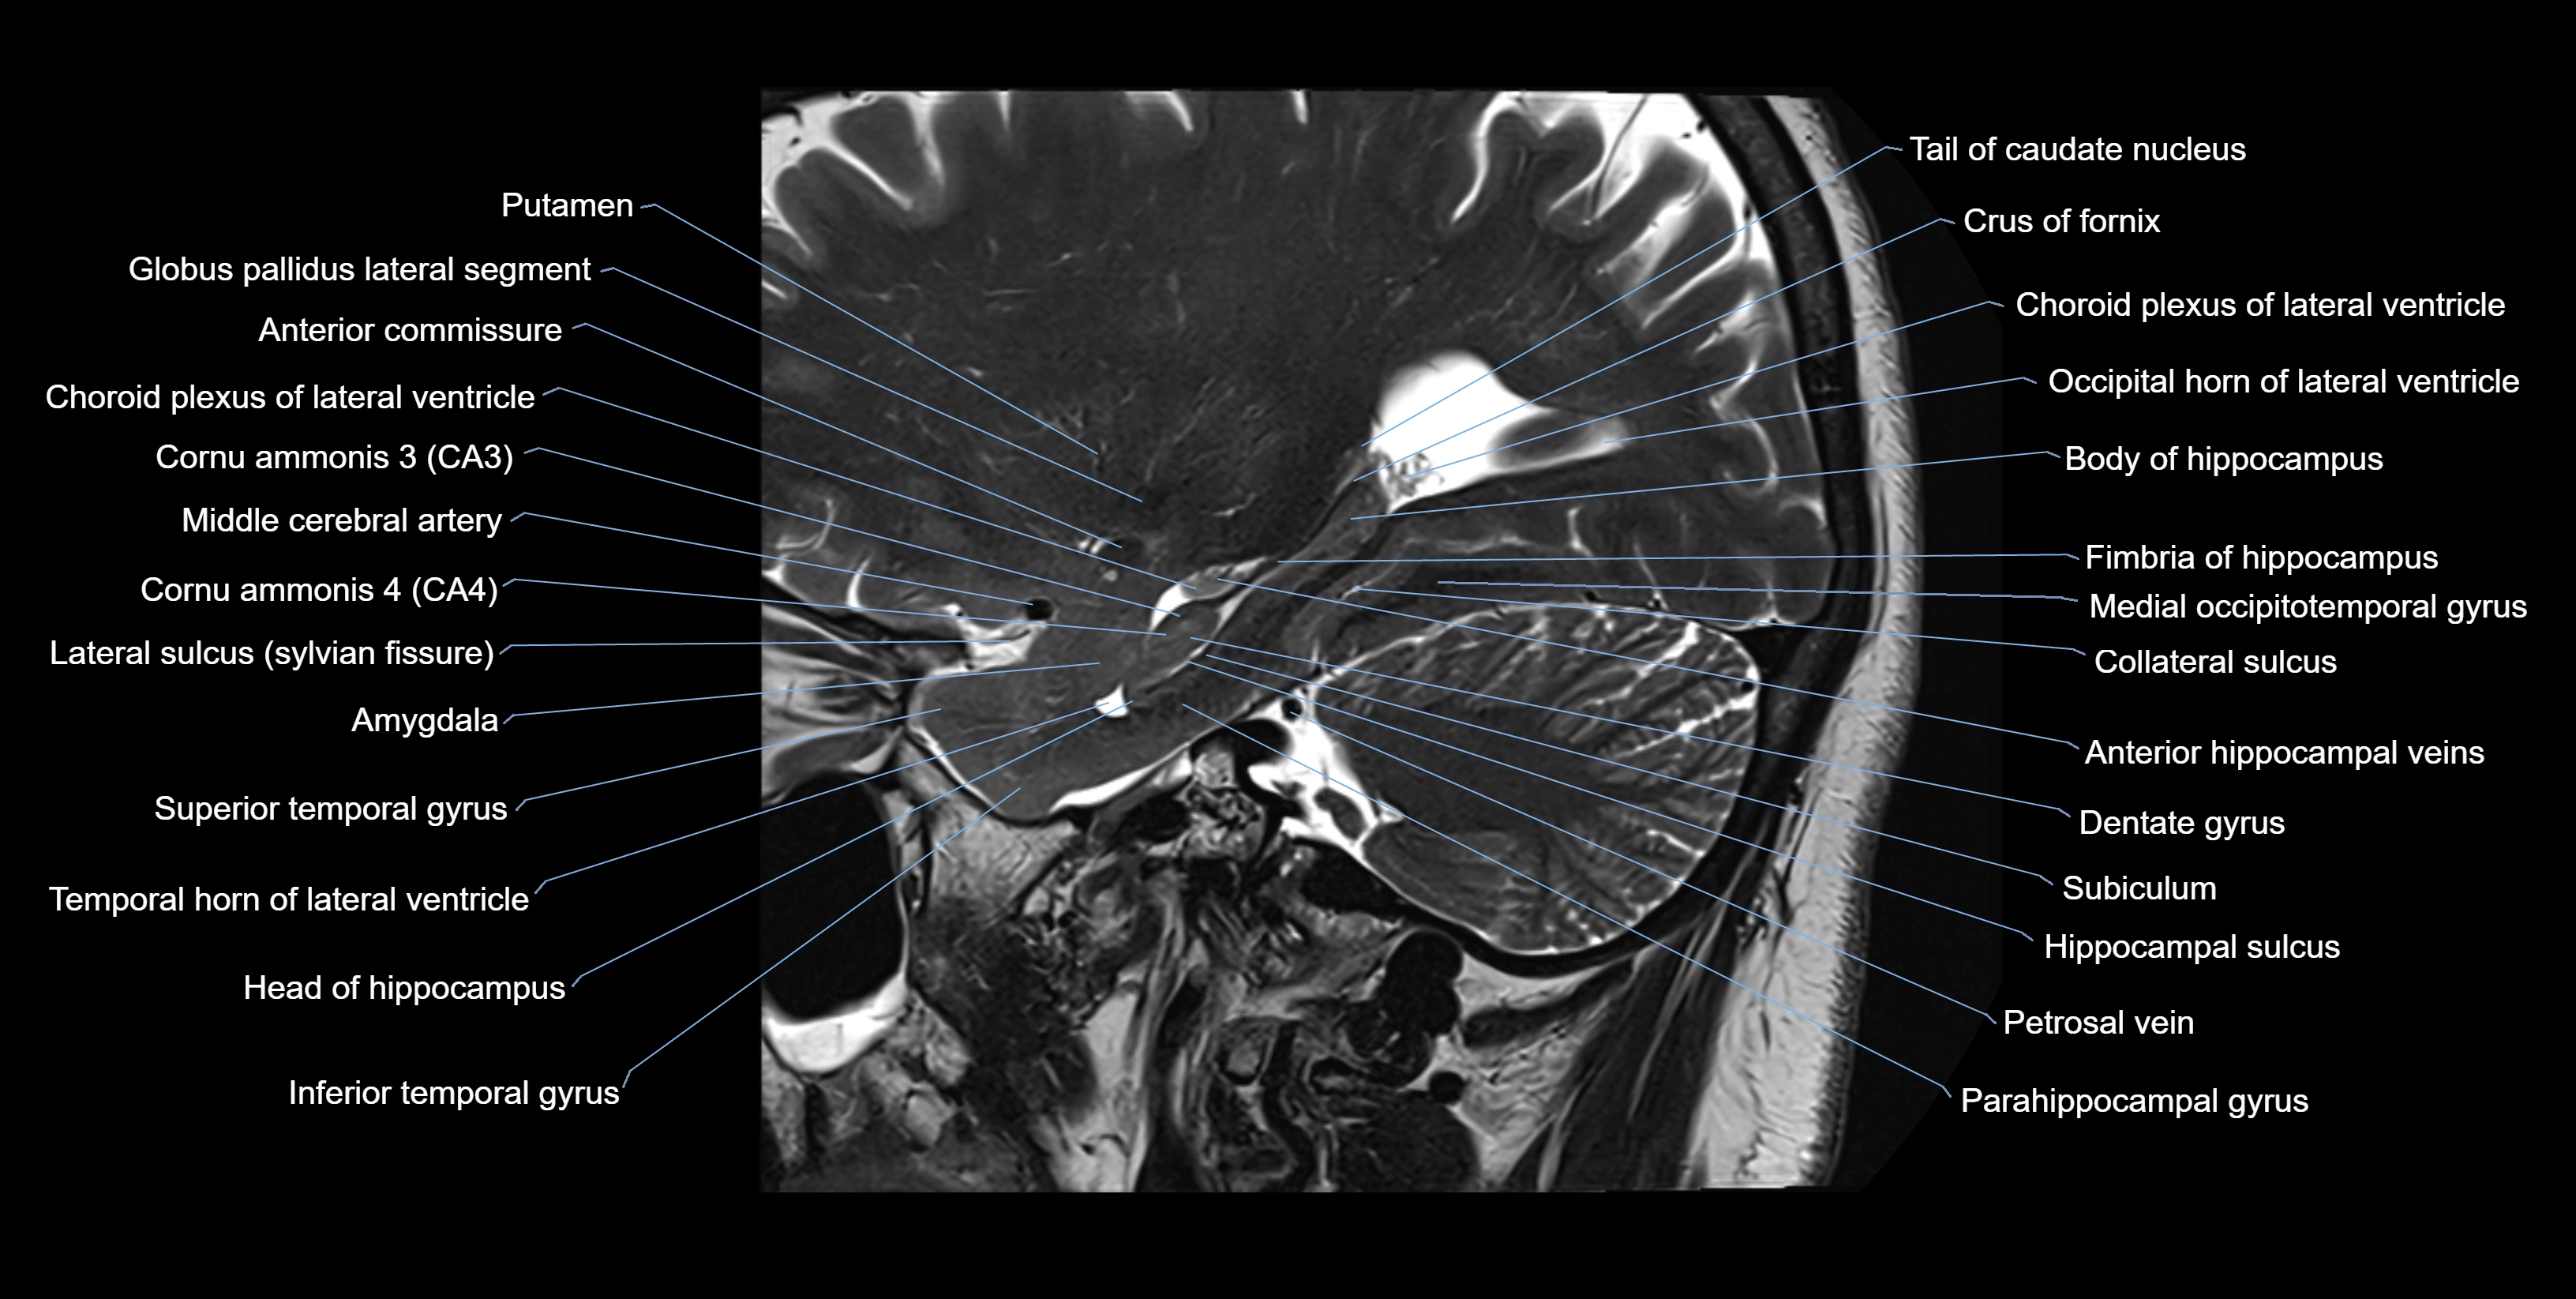

Location and Structure

• Position: Lies on the ventricular (superior) surface of the hippocampus, beneath the ependyma of the inferior horn of the lateral ventricle.

• Composition: A thin sheet of myelinated axons derived mainly from hippocampal pyramidal cells.

• Course: Fibers run medially along the hippocampal surface to form the fimbria of the hippocampus, which curves upward and backward into the fornix.

• Relations:

• Superiorly: Ependyma and CSF of the temporal horn of the lateral ventricle

• Inferiorly: Pyramidal cell layer of the hippocampus (CA1 region)

• Medially: Fimbria and fornix

• Laterally: Temporal lobe white matter and parahippocampal gyrus

MRI Appearance

T2-weighted images:

• Alveus: Low signal line overlying brighter hippocampal gray matter.

• CSF: Bright hyperintense.